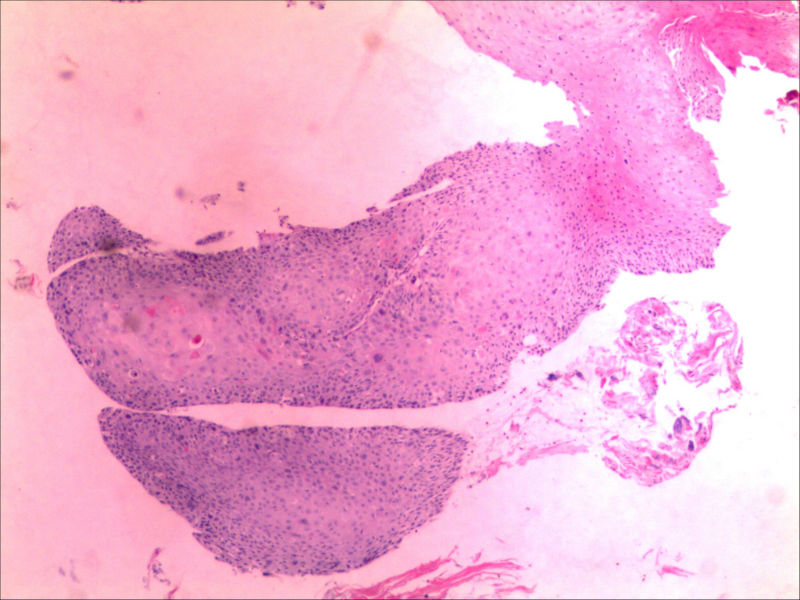

食管活检男64岁食管粗糙

图3